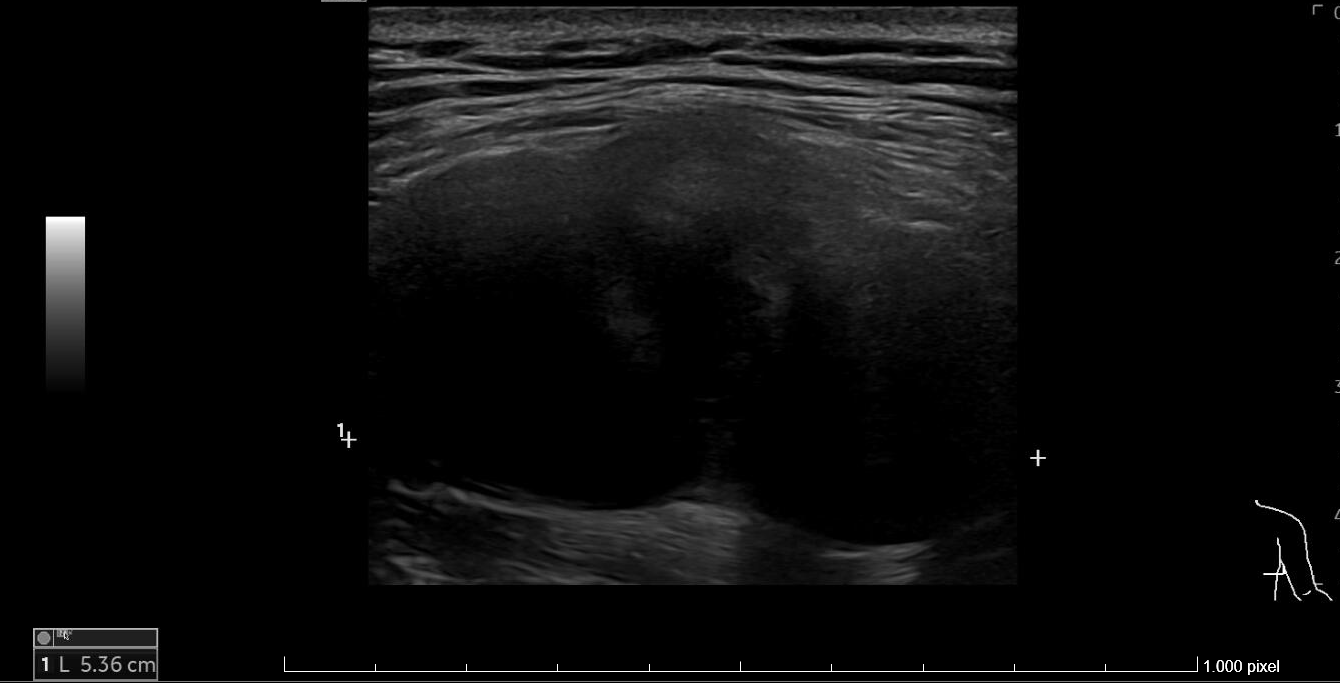

Ecografía: en el tercio medio y posterolateral de la pared torácica derecha, se observa una tumoración sólida, con densidad de partes blandas a nivel más craneal y un componente graso heterogéneo en el polo inferior, de aproximadamente 40 x 32 x 53 mm (transversal-AP-craneocaudal) que presenta pequeños vasos en su interior. Se sitúa en la en el plano muscular superficial, aproximadamente a 7 mm de profundidad respecto a la piel.